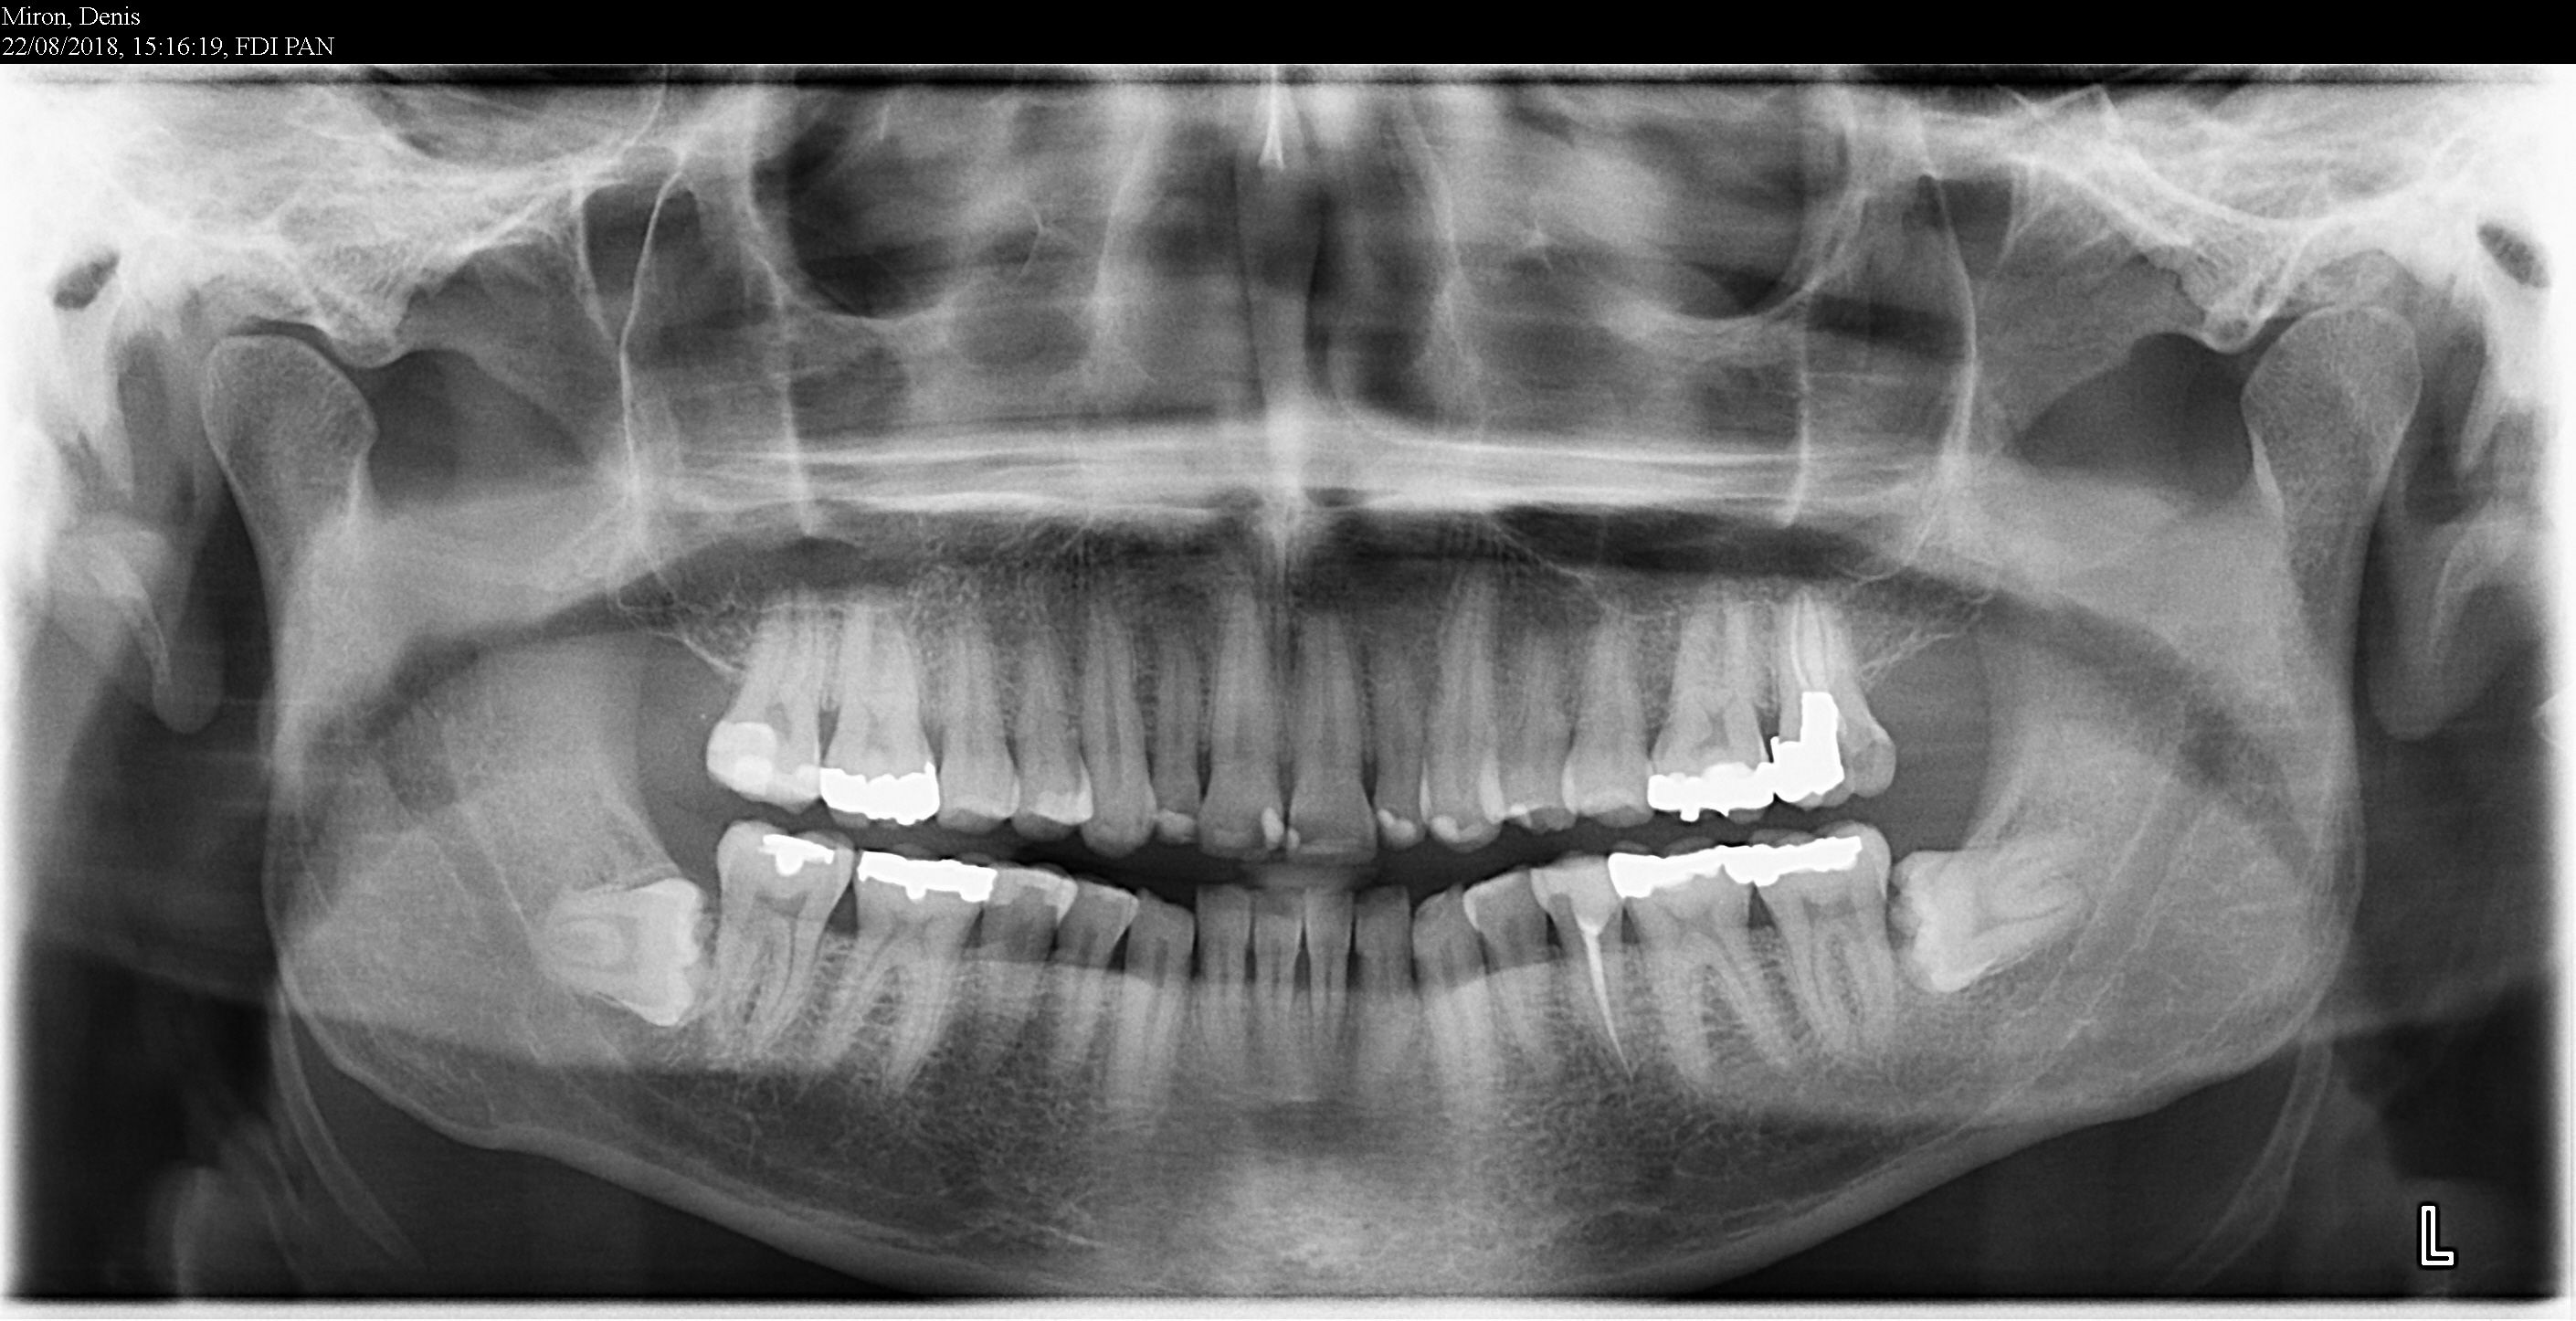

Les dents de sagesse, aussi appelées troisièmes molaires, sont les dernières dents à pousser tout au fond de notre cavité buccale. Elles se situent à l'arrière de la mâchoire, à l'âge adulte, entre 17 et 25 ans, parfois même plus tard. Les dents de sagesses poussent entre 17 et 21 ans en général

Dent de sagesse fautil toujours opérer. Dent de sagesse à 30 ans ? Voici nos conseils et solutions pour faire face à cette situation inattendue. Elles se situent à l'arrière de la mâchoire, à l'âge adulte, entre 17 et 25 ans, parfois même plus tard.